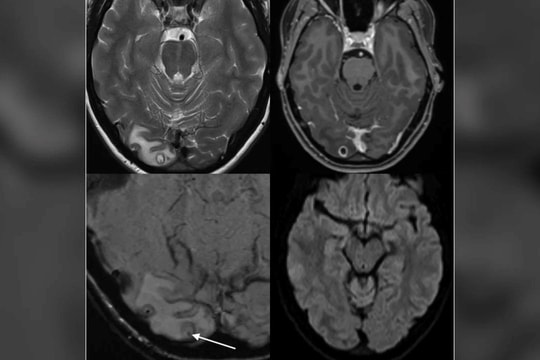

Thậm chí, ký sinh trùng này có thể đi khắp cơ thể, trong đó nguy hiểm nhất là gây tổn thương ở não, gan, phổi và mắt.